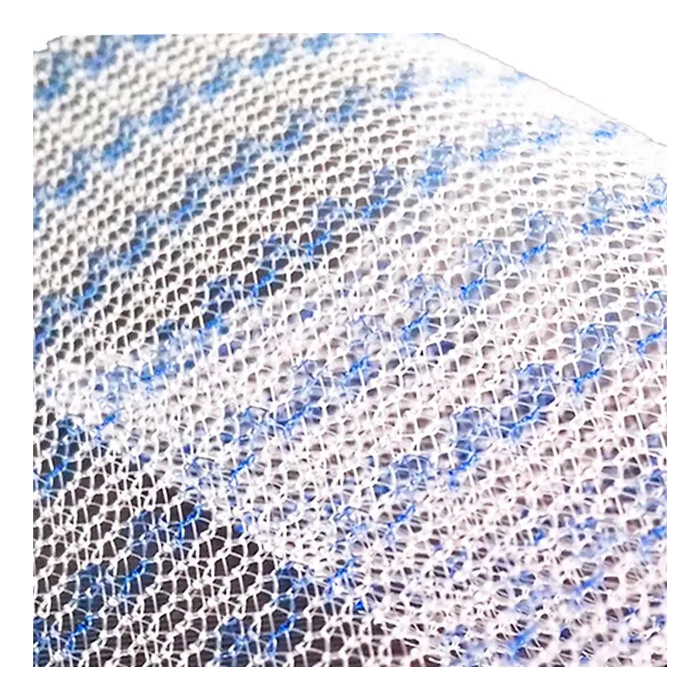

Эндопротез-сетка (сетка хирургическая) полипропиленовый для восстановительной хирургии ЭСФИЛ лёгкий, 15х15 см, Линтекс

Эндопротез-сетка полипропиленовая ЭСФИЛ лёгкий 15х15 см

Полипропиленовая хирургическая сетка ЭСФИЛ лёгкий от компании «Линтекс» — это современный высокотехнологичный имплантат, предназначенный для восстановительной и пластической хирургии. Изделие специально разработано для эффективного и безопасного укрепления тканей при операциях по устранению грыж различной локализации, коррекции дефектов передней брюшной стенки и в реконструктивной хирургии.

- Оптимальная интеграция в ткани: Макропористая структура сетки позволяет тканям свободно прорастать через ячейки, обеспечивая надежную фиксацию имплантата и равномерное распределение нагрузки.

| Структура | Макропористая, монофиламентная |